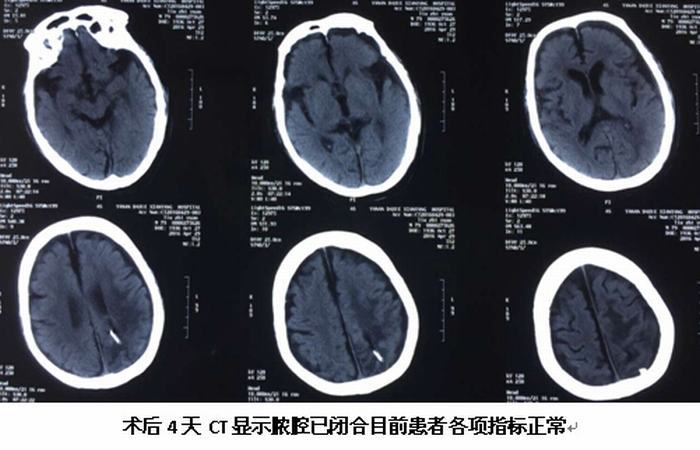

继完成第一例脑立体定向手术后不久,于2016年4月25日我院神经外科又完成一例89岁高龄脑脓肿患者的脑立体定向脓肿穿刺引流术,按照手术标准流程操作,术中清除脓液约30ml,经置管持续引流并局部及全身注射抗菌素治疗,目前患者头颅CT显示脓腔已消失,体温正常,神志清楚,各项生命体征平稳。